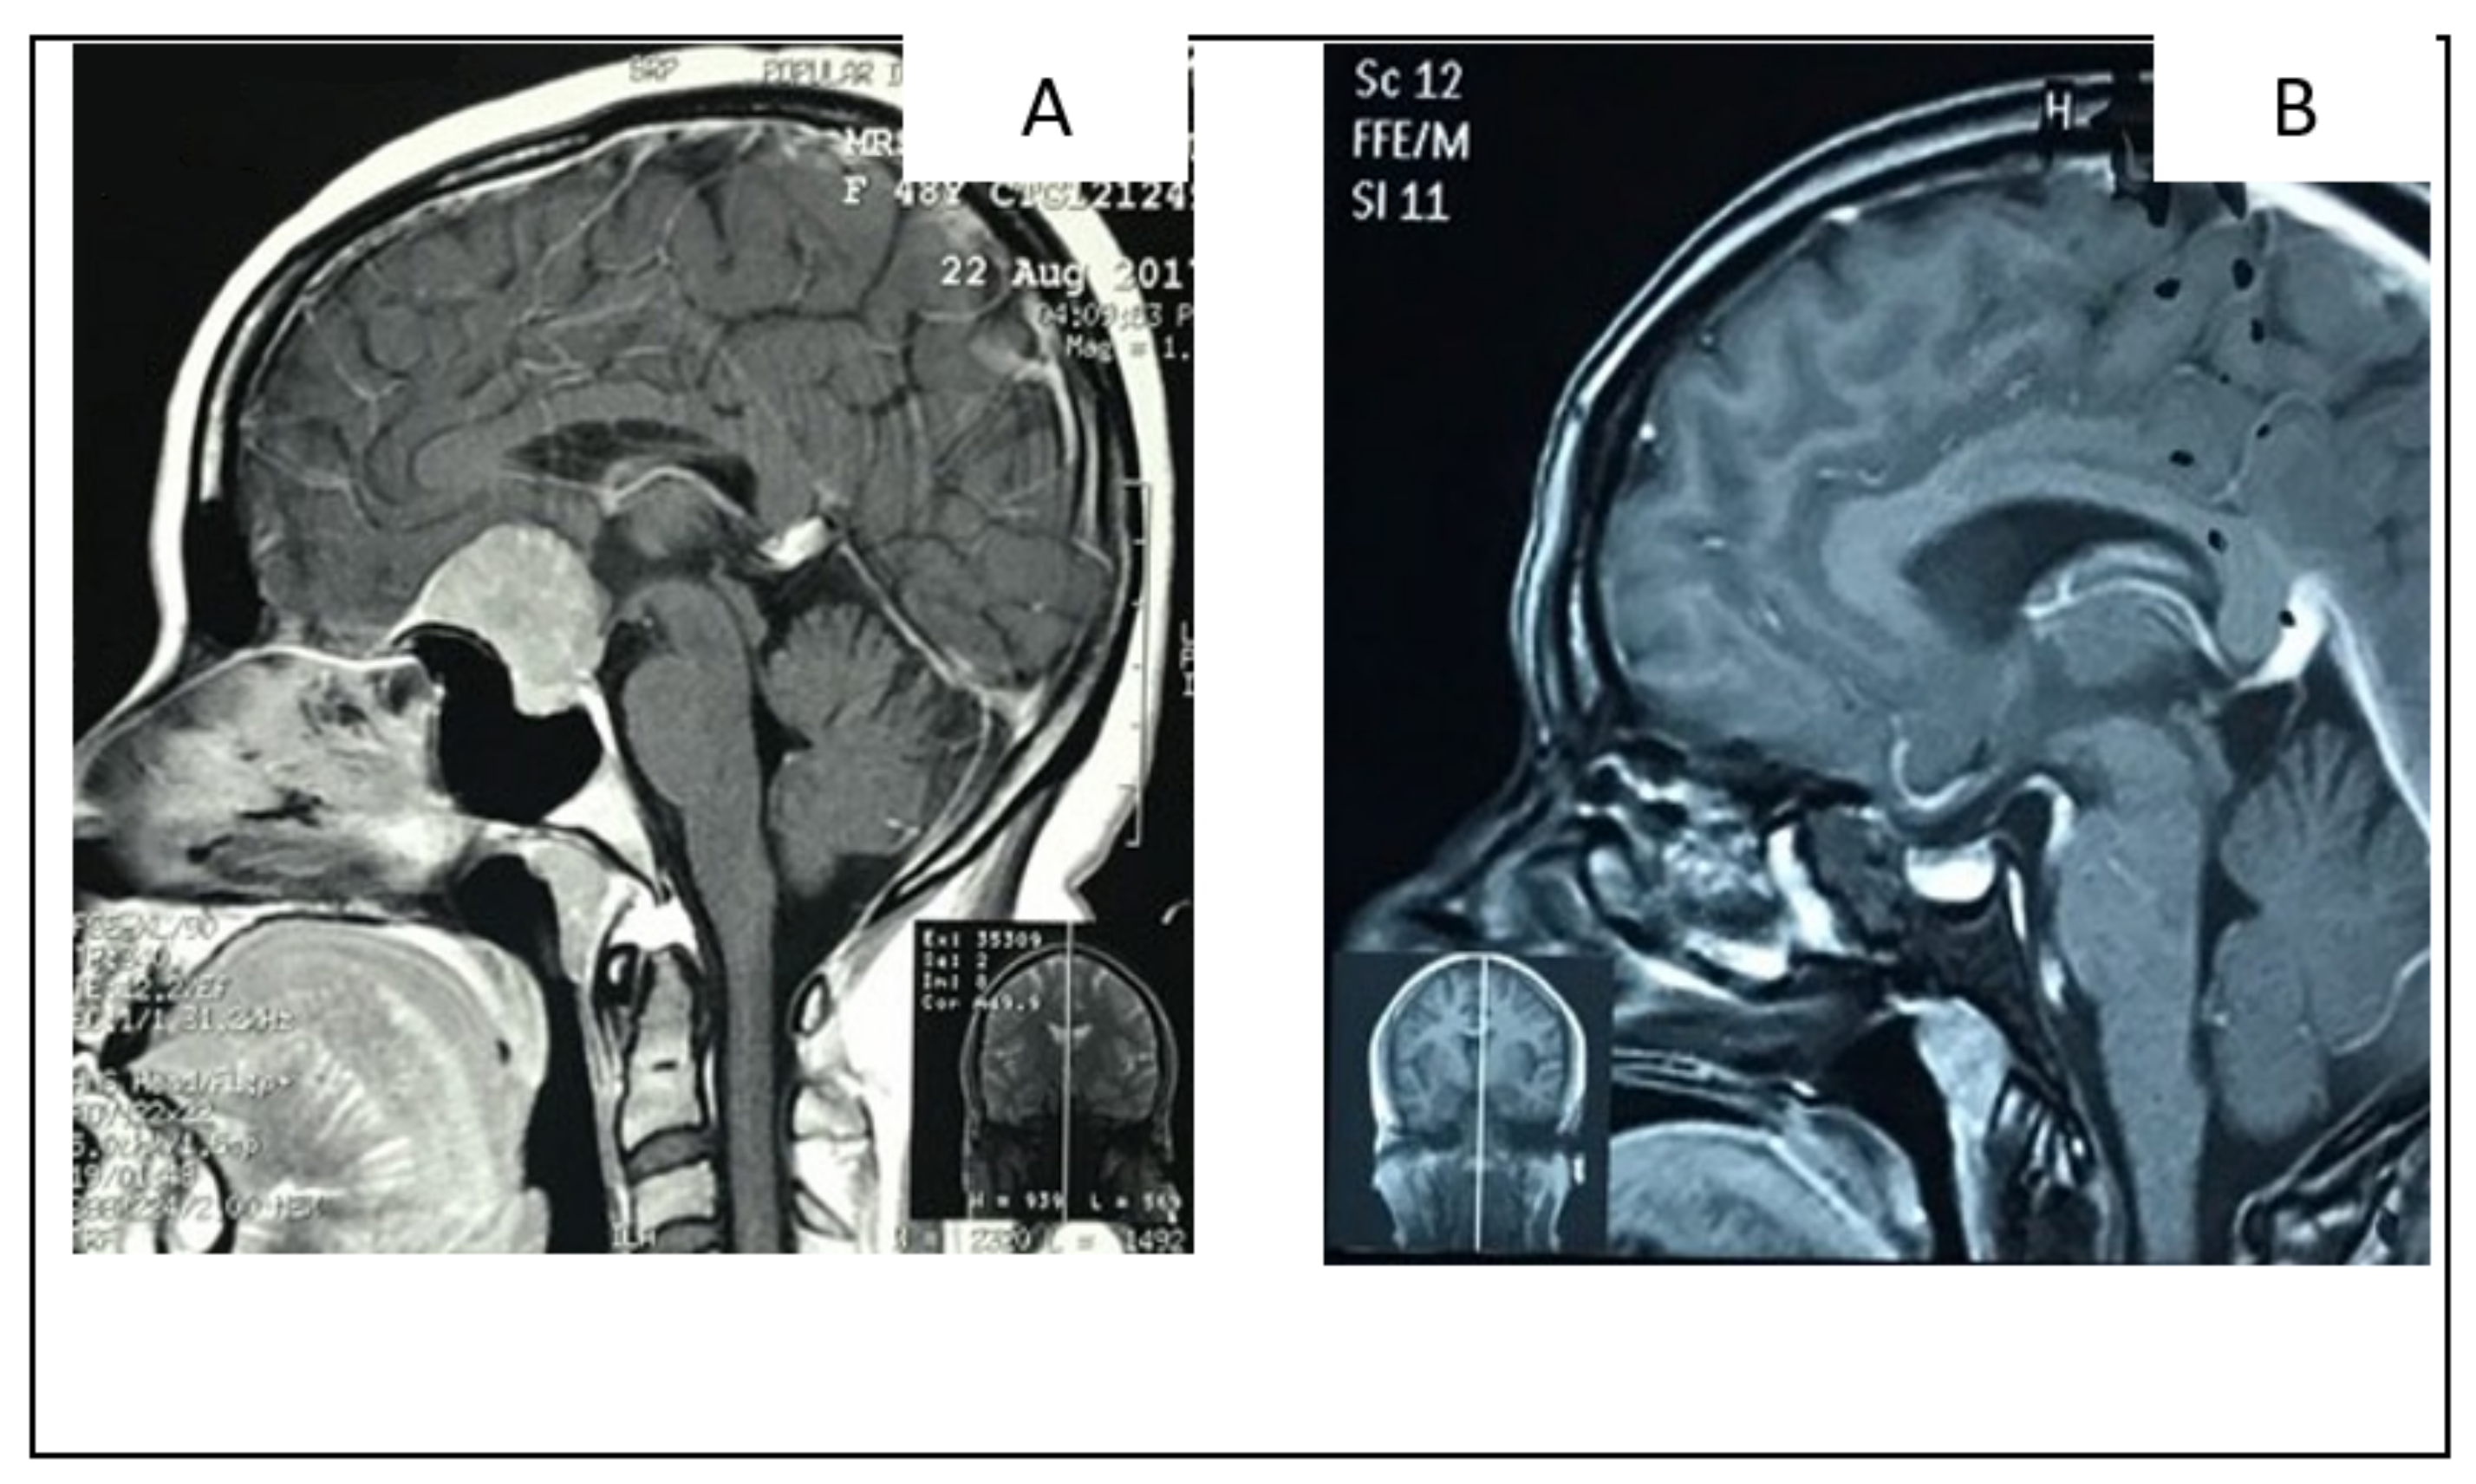

2.1.2. Illustrative Case: 1

2.2.2. Illustrative Case 2

2.3.2. Illustrative Case 3

2.4.2. Illustrative Case 4

2.5.2. Illustrative Case 5